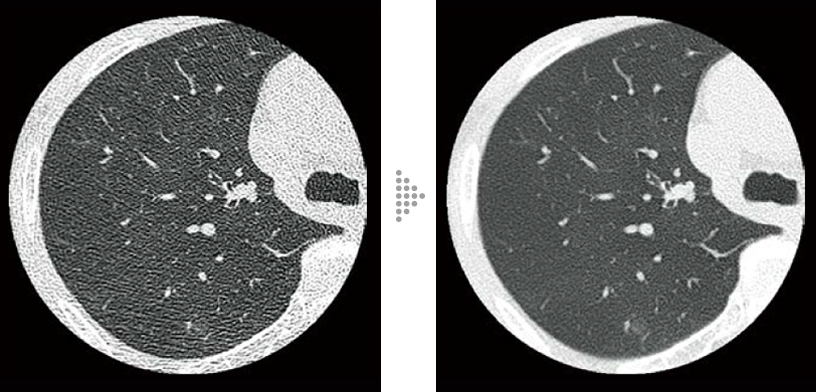

FBP(Left)

Intelli IPV(Right)

Lung screening (CTDlvol: 2.0 mGy)